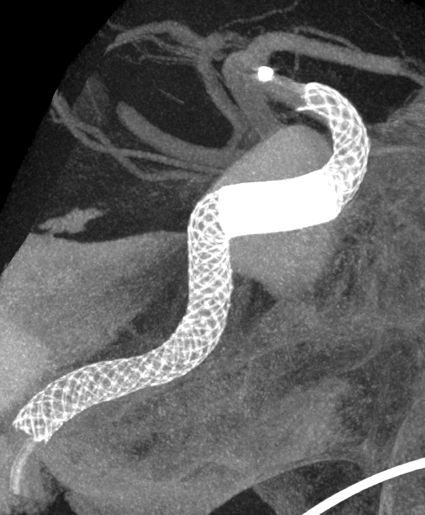

脳動脈瘤の新しい治療法「フローダイバーターステント」

脳動脈瘤に対する外科的治療は、従来頭を切って行う開頭クリッピング術に始まり、近年では血管内治療:カテーテルでの動脈瘤コイル塞栓術が進歩してきました。しかしコイル塞栓術は動脈瘤の形状、とくに動脈瘤の開口部(ネック)が広いものは、コイルが正常血管へ逸脱してしまい不向きとされていました。これに対してバルーンカテーテルでコイルが逸脱しないようにサポートする方や 、ステントというやわらかい金属を動脈瘤の入り口に留置し、コイルが正常血管に出てこないようにする方法が開発され、血管内治療の動脈瘤治療の適応が広がってきました。

しかし、大型の動脈瘤においては コイル塞栓術単独では時に再発することがあり 、開頭手術によりバイパスを併用して、動脈瘤を含む正常血管ごと止めてしまう方法が主流でした。

ところが2015年に本邦においてフローダイバーターステント治療が導入されました。

動脈瘤内にコイルを充填することなく、非常に編み目を細かくしたステントで、これを正常血管に留置することで脳動脈瘤内に流入する血液量を減少させます。すると脳動脈瘤内の血液がうっ滞し、徐々に血栓化して脳動脈瘤が完全に閉塞します。半年後に約75%、1年後に約85%が完全に閉塞すると言われています。このような新しい治療法が動脈瘤治療において今後も期待されています。

Apoplexy 21

【術前】

Apoplexy 22

【フローダイバーダー留置】

Apoplexy 23

【半年後】

フローダイバーター治療の放射線学的画像